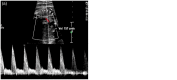

Figure 3

(a) Pulsed Doppler analysis of normal ductus arteriosus and (b) at the aneurysm showing bidirectional flow